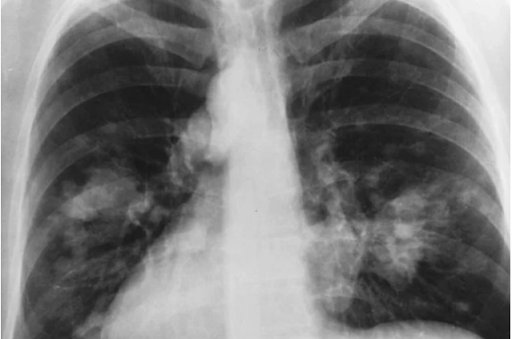

Gambar city scan paru-paru dilansir dari theasianparent.com

Hasil penelitian ini menemukan bahwa fungsi paru-paru perempuan yang menggunakan produk pembersih ternyata kondisinya sama dengan perokok yang mengisap sebungkus rokok sehari!

Ia melanjutkan, "Kami khawatir kalau bahan kimia semacam itu, jika terus menerus digunakan dapat menyebabkan kerusakan pada saluran napas. Dan ini berlangsung dari hari ke hari, dari tahun ke tahun, otomatis akan mempercepat laju penurunan fungsi paru-paru yang terjadi seiring bertambahnya usia," tambahnya.

Para ilmuwan juga menemukan bahwa perempuan yang rutin menggunakan produk pembersih rumah lebih rentan terhadap asma. Produk ini juga memiliki dampak negatif pada kapasitas paru-paru mereka.